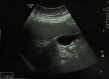

Psammocarcinoma is an uncommon subtype of low-grade serous carcinoma. It is characterized by the presence of extensive psammoma bodies and can have either an ovarian or peritoneal origin. To our knowledge fewer than 30 cases of primary peritoneal psammocarcinoma (PPP) have been reported in the English literature. We report a rare case of PPP in a 74-year-old female, discovered fortuitously within a laparotomy for gallbladder lithiasis. At laparotomy, multiple nodular implants involving the omentum, the peritoneum and a magma of intestinal loops in the right iliac fossa were noted. A biopsy from nodules was performed. Gross examination showed multiple nodules of different sizes in the fat tissue. Pathologic examination showed massive psammoma bodies representing more than 75% of the tumor. The final diagnosis was psammocarcinoma. Our patient was referred to the gynecologic department for further investigation and to ascertain whether the tumor arose from the ovaries or peritoneum. Hysterectomy, bilateral adnexectomy and omentectomy were performed. Macroscopic examination showed that both ovaries were intact having a normal size. No invasion of ovarian stroma was shown in microscopic examination. The patient died of SARS-CoV-2 (COVID-19) six days after the surgery. PPP is a rare type of low-grade serous carcinoma. The behavior of this tumor is unclear, and the treatment is not standardized because of its rarity and lack of long-term follow-up. More cases need to be studied for better understanding and improvement of the management protocols.